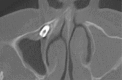

Purpose: To report the clinical and radiological characteristics of a patient who experienced dental implant displacement into the maxillary sinus following sinus floor elevation, and to compare our findings with those of other published reports of the displacement of dental implants.

Materials and methods: Implant placement and maxillary sinus elevation were performed simultaneously. The location of the displaced implant was monitored for 8 years, until the ectopic implant was surgically removed using the lateral window approach. The contributing factors, treatment modality, and clinical outcome for our patient were compared with those of patients reported in the literature.

Conclusions: Transnasal endoscopic removal of an ectopic implant may be suitable in cases in which the ectopic implant is accessible. Transoral direct approaches are adequate in most cases in which endoscopic approaches may be confounded. The bony-window transoral technique may allow the removal of large implants.